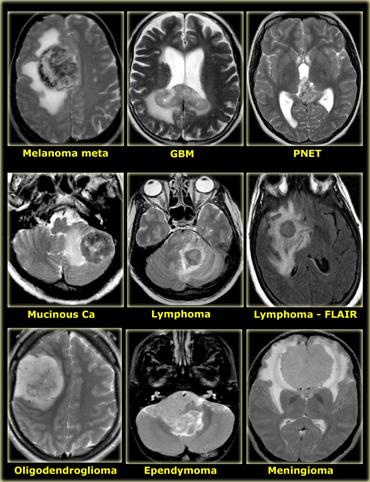

Hình bên trái là một số ví dụ về các khối u có cường độ tín hiệu thấp trên chuỗi xung T2W.

- Di căn u hắc tố có tín hiệu thấp trên chuỗi xung T2W do melanin.

- GBM có thể có tín hiệu thấp trên chuỗi xung T2W vì đôi khi chúng có tỷ lệ nhân-bào tương cao. Tuy nhiên, hầu hết GBM tăng tín hiệu trên chuỗi xung T2W.

- PNET thường có tỷ lệ nhân-bào tương cao. PNET chủ yếu nằm ở vùng não thất IV, nhưng một vị trí khác ít gặp hơn là vùng tuyến tùng.

- Di căn từ ung thư nhầy (mucinous metastases) có thể có tín hiệu thấp trên chuỗi xung T2W vì chúng thường chứa vôi hóa.

- U màng não (meningioma) thường có tín hiệu trung gian.

Chúng có thể có tín hiệu cao trên chuỗi xung T2W nếu chứa nhiều nước.

Chúng có thể có tín hiệu thấp trên chuỗi xung T2W nếu rất đặc và tăng sinh tế bào cao hoặc khi chứa vôi hóa.